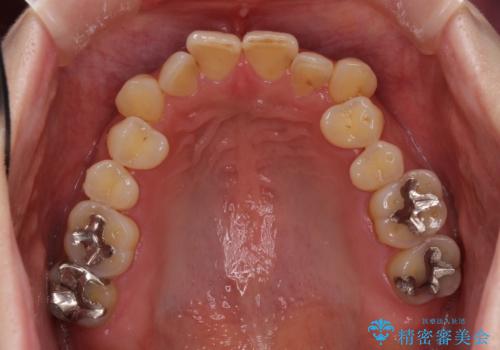

- 歯列不正と、どこで咬んで良いのか分からない咬み合わせを気にして来院された患者様です。

下顎骨は左側にシフトしており、咬み合ったときには奥歯と前歯の一部しか接触していない状態でした。

骨格的な左右差は歯列矯正は改善できないため、上下歯列が全体的に接触することをゴールとしてインビザラインにて矯正治療を行うこととしました。